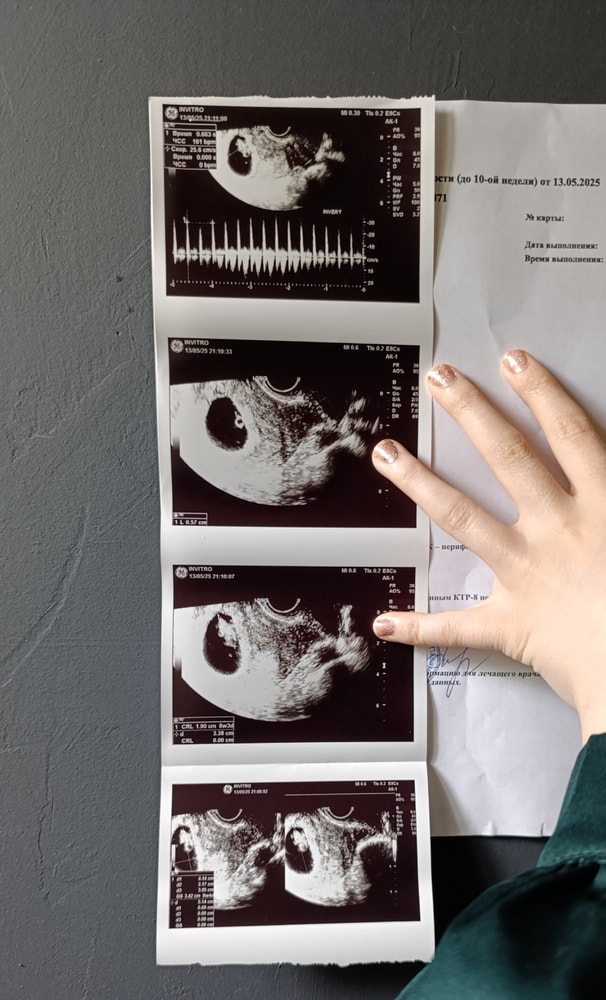

Узи 8нед+3дня

УЗИСходили на узи и... мы растём. Идём срок в срок. Такая там прелесть крошечная, столько счастья и радости, что словами не передать. А ведь когда шла так волновалась, потому что симптоматика притихла, вроде как есть, но слабая с попеременным нагнетанием.

Кстати, дали послушать сердечко, такое бойкое и громкое, ух!